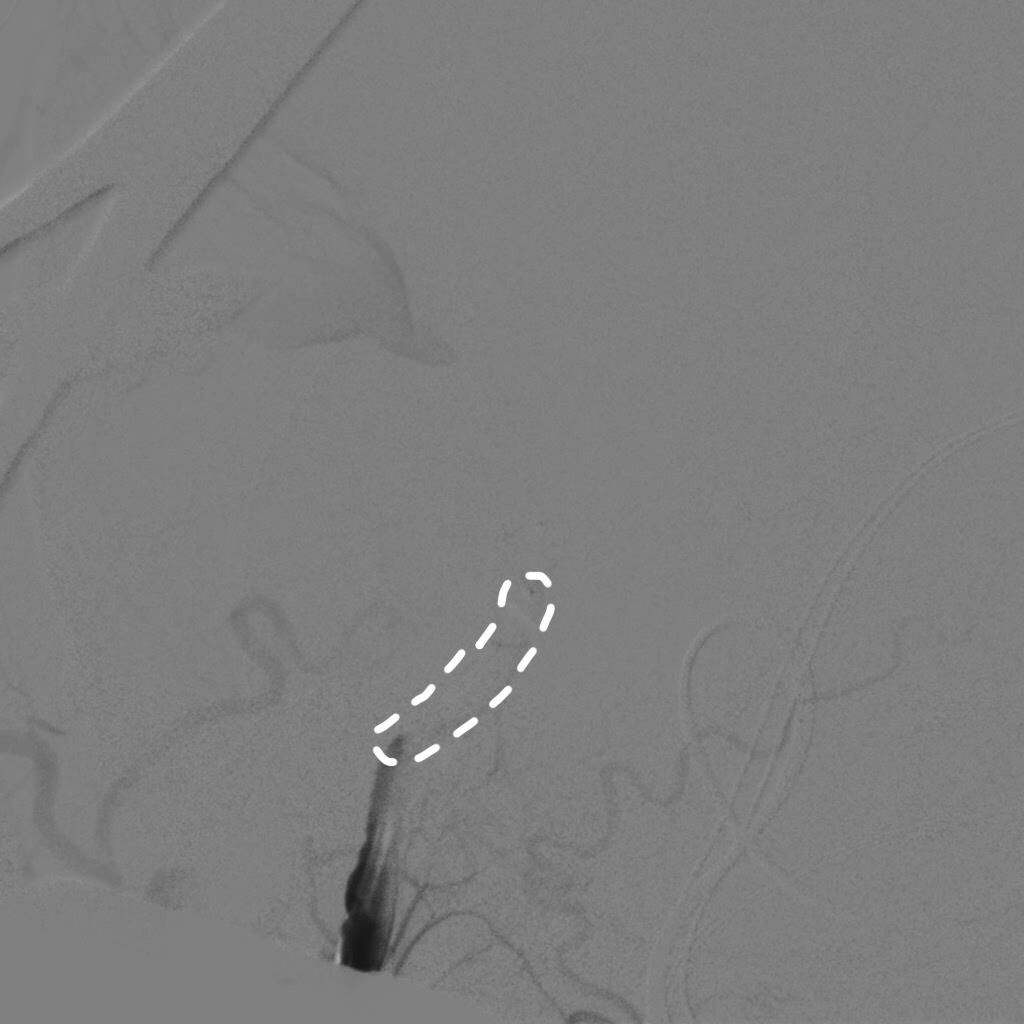

全身肝素化后,路图下将6FGuiding导引导管放置于右侧颈内动脉岩谷水平段,使用Scepter球囊微导管在014微导丝带领下超选进入颈内动脉岩谷垂直段,充盈球囊,造影显示阻断颈内动脉满意后继续手术。

球囊充盈,虚线为球囊

球囊阻断满意,造影剂返流至颈外动脉,虚线为球囊

再次探查动脉瘤发现瘤体表面张力明显下降,探针分离瘤颈,以2枚直动脉瘤夹792+760夹闭瘤颈。解除球囊阻断后,动脉瘤表面张力无回升,穿刺瘤体无活动性出血。荧光造影提示瘤体无显影,载瘤动脉血流通畅,无明显狭窄,各分支保留完好。切除部分瘤体,视神经减压。DSA复查提示动脉瘤夹闭满意,全脑血管通畅后关颅。(球囊阻断时间约10分钟)